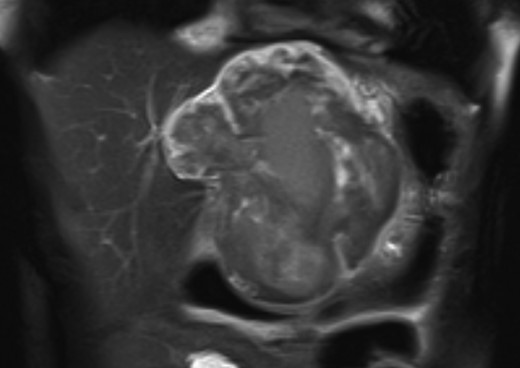

An 18-year-old woman presented with epigastric pain that started during a Japanese drum lesson. She was diagnosed with rupture of a hepatic tumor and transported to our hospital. She had no medical history of surgery, including abdominal surgery. Contrast-enhanced computed tomography (CT) revealed a 13-cm, low-density giant mass in the left hepatic lobe and high-density ascites, indicating abdominal bleeding from the liver tumor (Fig. 1). Ultrasonography confirmed a well-defined giant mass of the liver, comprising both cystic and solid lesions. Laboratory data showed a low hemoglobin level of 8.2 g/dl, and all the results of liver function tests and tumor marker measurement were within normal ranges. The patient underwent emergent celiac angiography, which revealed an avascular tumor with no evidence of extravasation from the hepatic artery. The left hepatic artery was considered to be the artery feeding the tumor and was embolized (Fig. 2). Magnetic resonance imaging (MRI) confirmed a well-defined giant multilocular lesion with fibrous partition (Fig. 3). After the patient's condition stabilized, she underwent left hepatic lobectomy. Laparotomy revealed bloody ascites and a large tumor in the left lobe of the liver; the right lobe appeared normal. The enlarged lymph nodes of the hepatoduodenal ligament were also dissected. Histological analysis of the resected specimen revealed a huge cystic mass of ∼12 × 9.5 cm. The mass was cystic and multilocular with a fibrous wall and filled with a massive blood clot (Fig. 4). The enlarged lymph node had a 25 × 23-mm cyst, which contained yellowish fluid. On microscopic examination, the wall of the cyst consisted of a tight elastic fiber meshwork composed of collagen fibers, which was accompanied by a small amount of acid mucopolysaccharide in the stroma and a lining of single-layered flat cells on the inner wall (Fig. 5a and b). Immunohistochemical staining revealed that the cyst wall was positive for both the endothelial marker CD31 and the lymphangial marker D2-40 (Fig. 5c and d). The cystic structure of the lymph node also was composed of elastic fiber components similar to those of the cyst in the liver and lined with single-layered flat cells, which were immunohistochemically positive both for CD31 and D2-40 (Fig. 5e). The pathological diagnosis was hepatic lymphangioma combined with lymphangioma of the lymph nodes. The patient's postoperative course was uneventful, and she was discharged on Day 8. During follow-up for almost 4 years since the surgical treatment, the patient has presented no sign of recurrence.

MRI confirmed a well-defined giant multilocular lesion with fibrous partitioning.